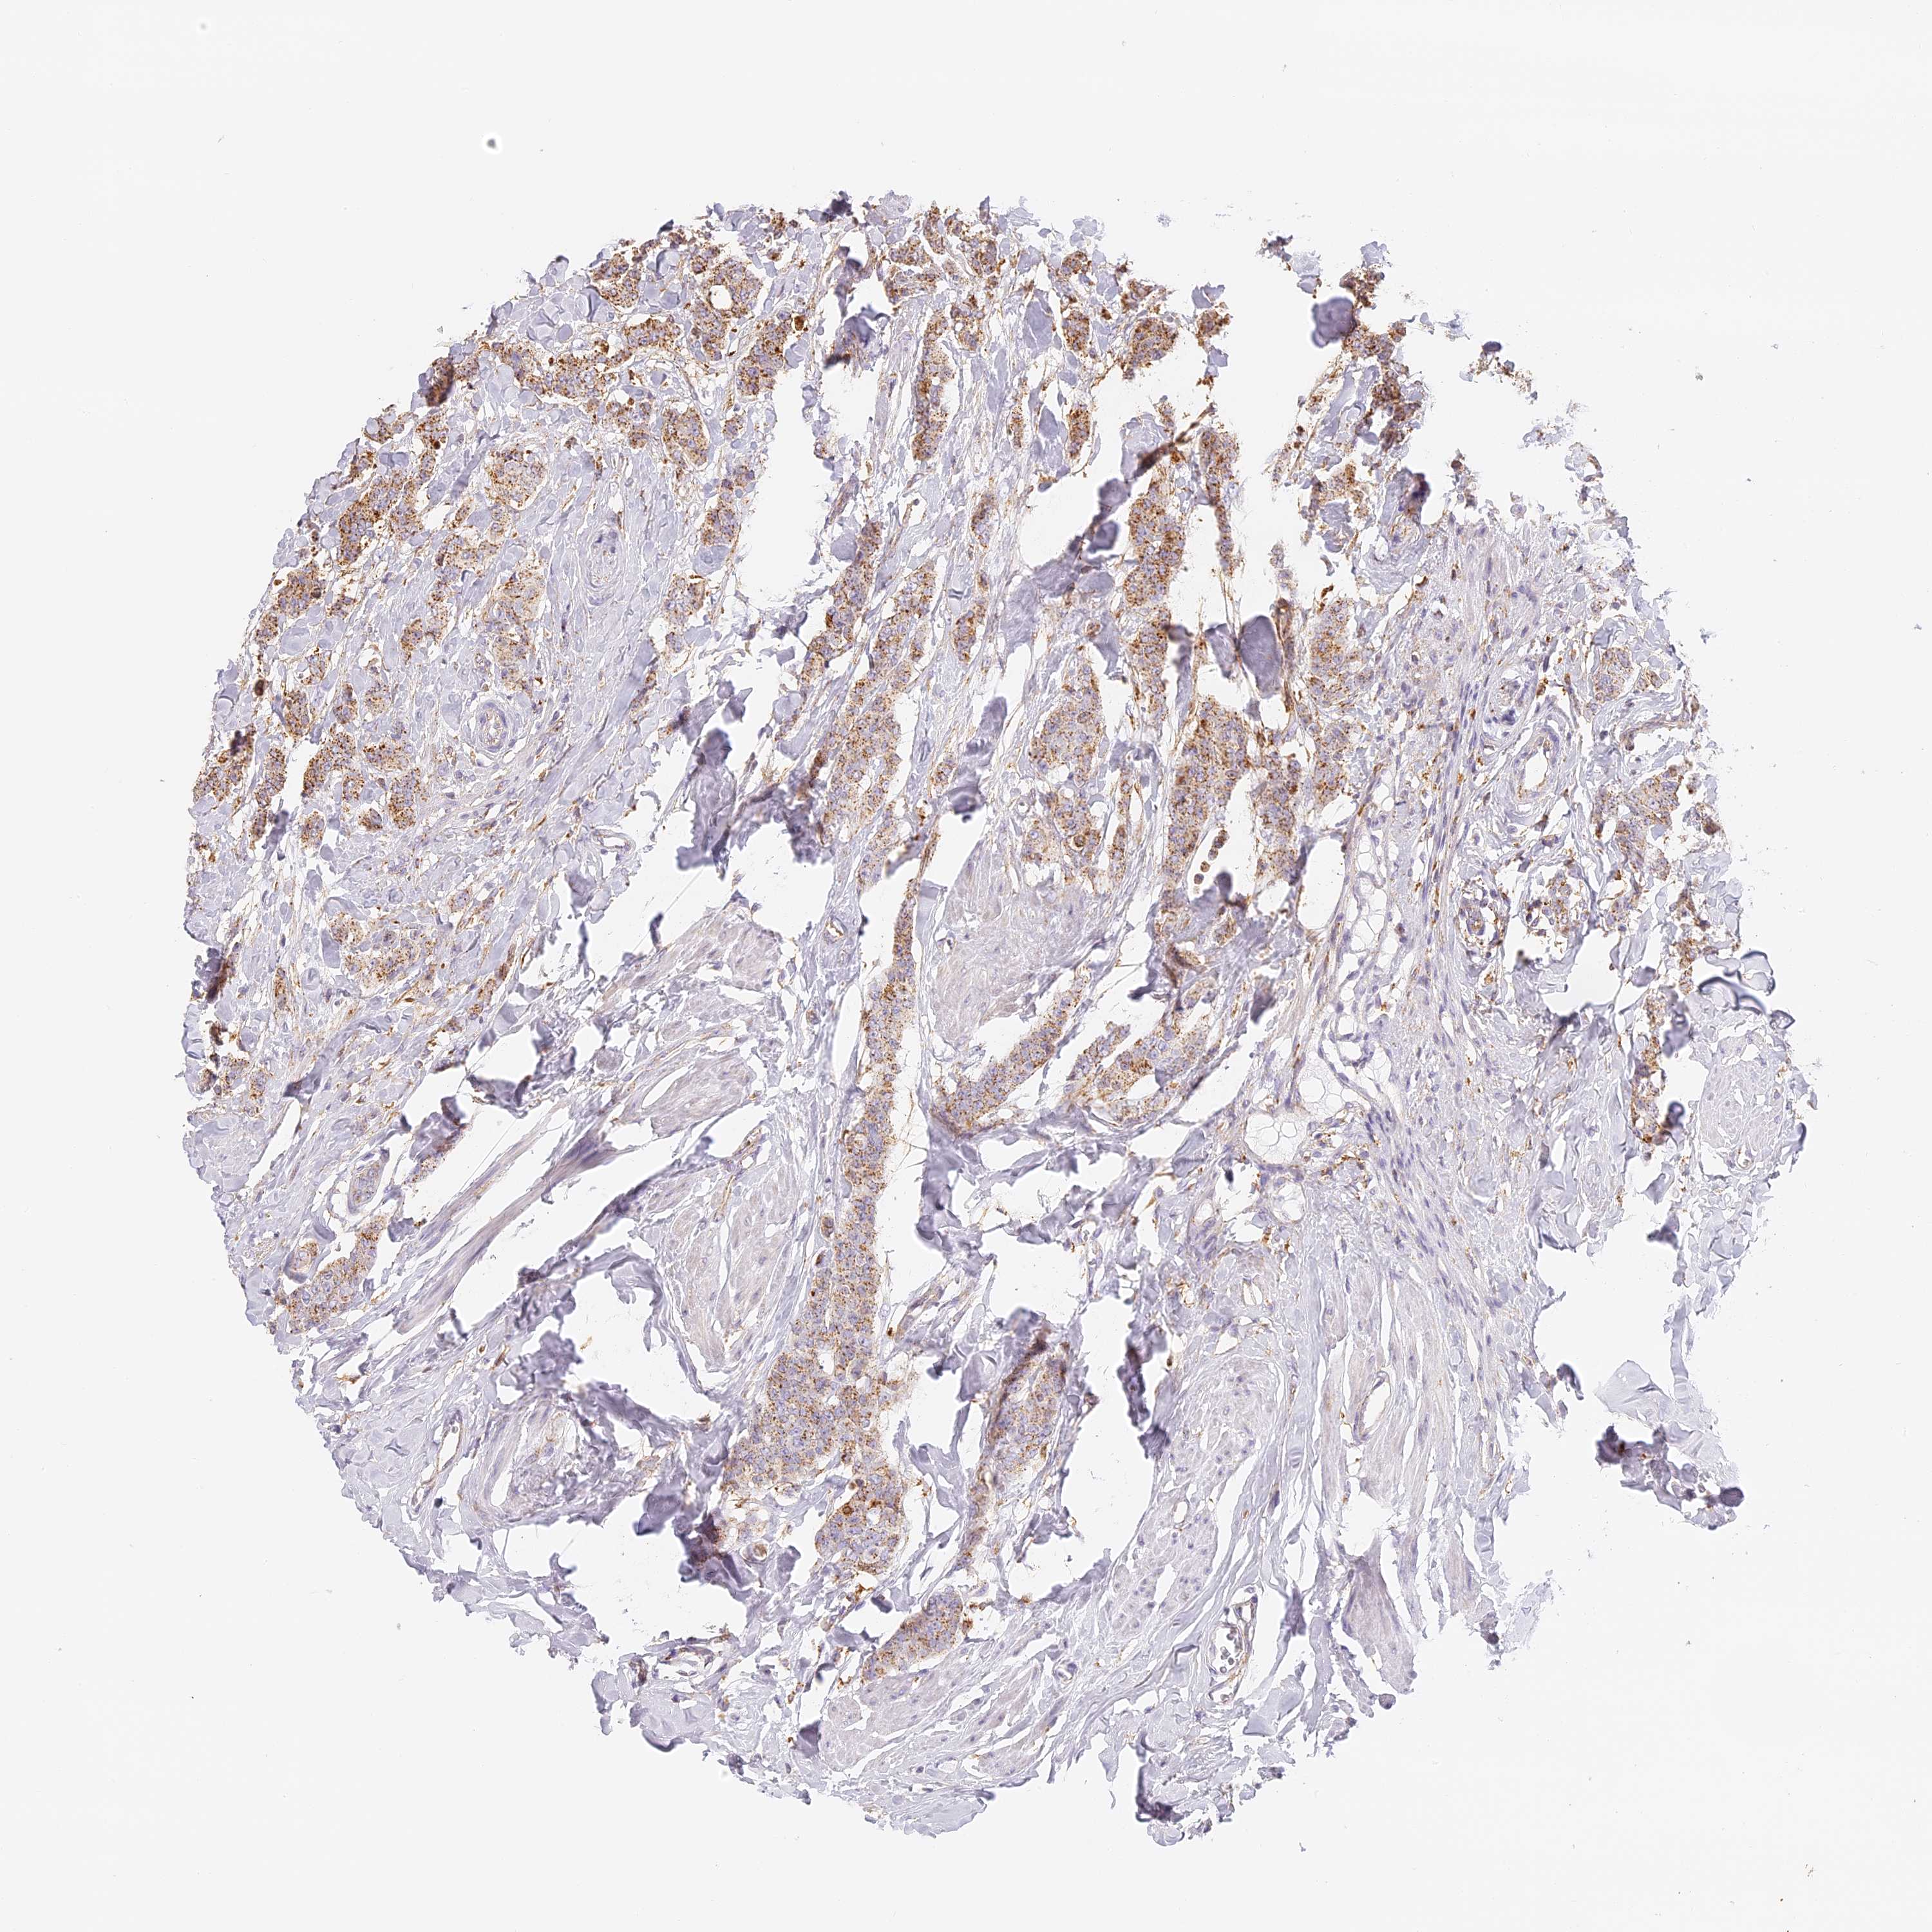

CANCER BREAST CANCER Show tissue menu

BRCA TCGA BRCA VALIDATION PROTEIN EXPRESSION